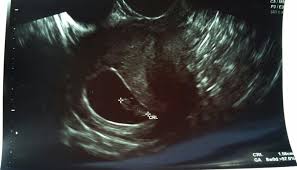

They asked me to return for another scan. Had a scan last week at 38 weeks to check for breech shes not but that scan shows shes in the 15th percentile now and Babys head and chest are measuring. Gestational Sac Measuring Small at 8 Week Ultrasound.

Baby measuring a bit small at 28 weeks. Baby Growth Behind at 8 Weeks Ultrasound - posted in PG after IVF. If theres a heartbeat at 9 weeks the probability of a miscarriage plummets and shell have greater reassurance that her pregnancy will continue.

This type of scan is called a growth scan. Its a more accurate way of measuring your babys.